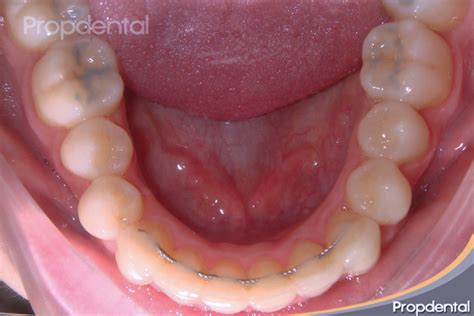

Muchos pacientes nos preguntan si la ortodoncia, bien sea Invisalign o brackets, se pueden poner solo arriba o solo abajo. El motivo es que tan solo tienen un colmillo en una arcada que está en mala posición, o un diente en la fila inferior que está algo desplazado. Es cierto que en casos muy, muy concretos, y siempre y solo tras decidirlo en una revisión en una clínica de ortodoncia, puede ser que solo haga falta los brackets de arriba o los de abajo.

Pero siempre estamos hablando de casos excepcionales, lo normal, lo más habitual y lo más recomendable es usar una ortodoncia completa. La ortodoncia es mucho más que tener los dientes de arriba o de abajo alineados.

Cuando realizamos un tratamiento de ortodoncia, ya bien sea con brackets o con alineadores transparentes, buscamos llevar los dientes a una posición de salud y a una correcta relación con el hueso. Esta expansión hace que la forma de la arcada dentaria cambie, por eso en la mayor parte de los casos es necesario poner brackets arriba y abajo, y no es posible poner brackets solo en una parte. La parte de arriba debe estar coordinada con la parte de abajo para que haga correctamente su función.